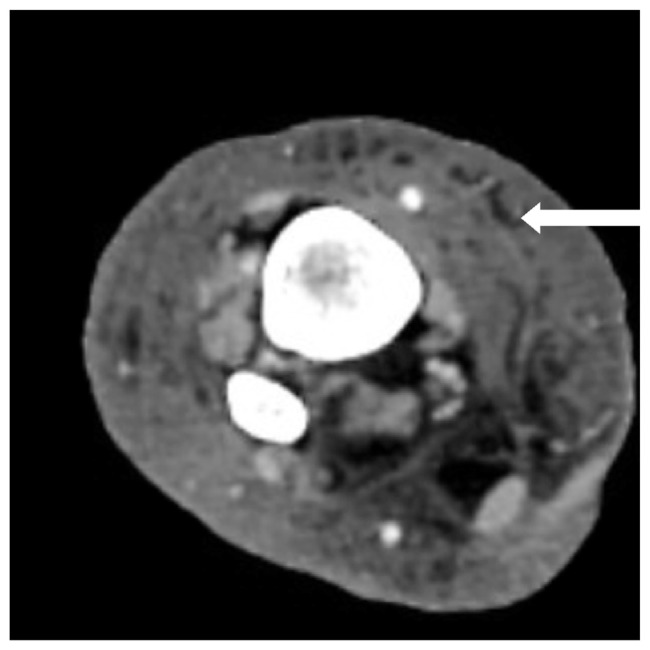

Pseudomonas putida is a rod-shaped, flagellated, non-lactose fermenting, gram negative bacterium, usually found in water and soil habitats. P. putida generally causes nosocomial infections in immunocompromised patients. Increased infection rates are seen in those patients with medical devices inserted, due to this organism's innate ability to attach to moist and inanimate objects. In this case report we present a 63-year-old male patient with a past medical history of type II diabetes mellitus, chronic kidney disease stage 5, and hypertension who presented with P. putida cellulitis and bacteremia. This patient had no exposure to contaminated water sources or soil; however, had immunocompromising comorbidities such as diabetes and chronic kidney disease. The patient was treated with intravenous (IV) antibiotics with vancomycin and cefepime which was de-escalated within 48 hours after obtaining sensitivity data from the blood cultures. The patient had an uneventful recovery and was discharged home in a stable condition. This case highlights the importance of considering P. putida as a potential pathogen in immunocompromised patients with no direct exposure to typical environmental sources. Prompt identification and targeted antimicrobial therapy is necessary for a favorable outcome.